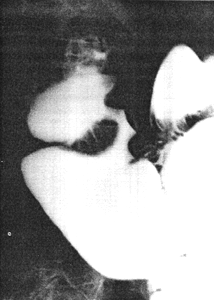

Physical examination revealed epigastric tenderness. A radiographic study, done elsewhere, showed an irregular narrowing 3.5 cm in length at the pylorus (Fig. 31.1A); it had been interpreted as a carcinoma. Repeat radiological examination showed that the narrowing was in reality a fistulous connection between the distal end of the pyloric sphincteric cylinder and the base of the duodenal bulb on the lesser curvature side. It was adjacent to, and located on the posterior aspect of the pylorus. The sphincteric cylinder remained partially contracted as illustrated, neither maximal contraction nor maximal expansion occurring. The duodenal bulb was deformed. The condition was diagnosed as an acquired double pylorus, i.e. a pyloroduodenal fistula as a result of a perforating ulcer. Endoscopy showed a benign pyloric ulcer filled with necrotic material. It had perforated into the duodenum and the instrument could be manipulated into the duodenum through the pylorus as well as through the channel formed by the perforation.

A![]() | B![]() |

| Fig. 31.1 A,B. Case S.K. A Narrow, irregular channel between pyloric sphincteric cylinder and duodenal bulb, diagnosed as carcinoma. Normal pyloric aperture not filled with barium. Cylinder partially contracted. B Resection specimen. Arrow through pyloroduodenal fistula. Pyloric aperture visible behind arrow | |